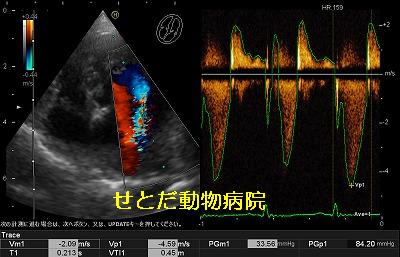

エコー検査で心臓を詳しく調べてみると左心室と左心房の間にある僧帽弁が閉じたときにすきまが出来て血液が逆流する「僧帽弁閉鎖不全症」とわかりました。